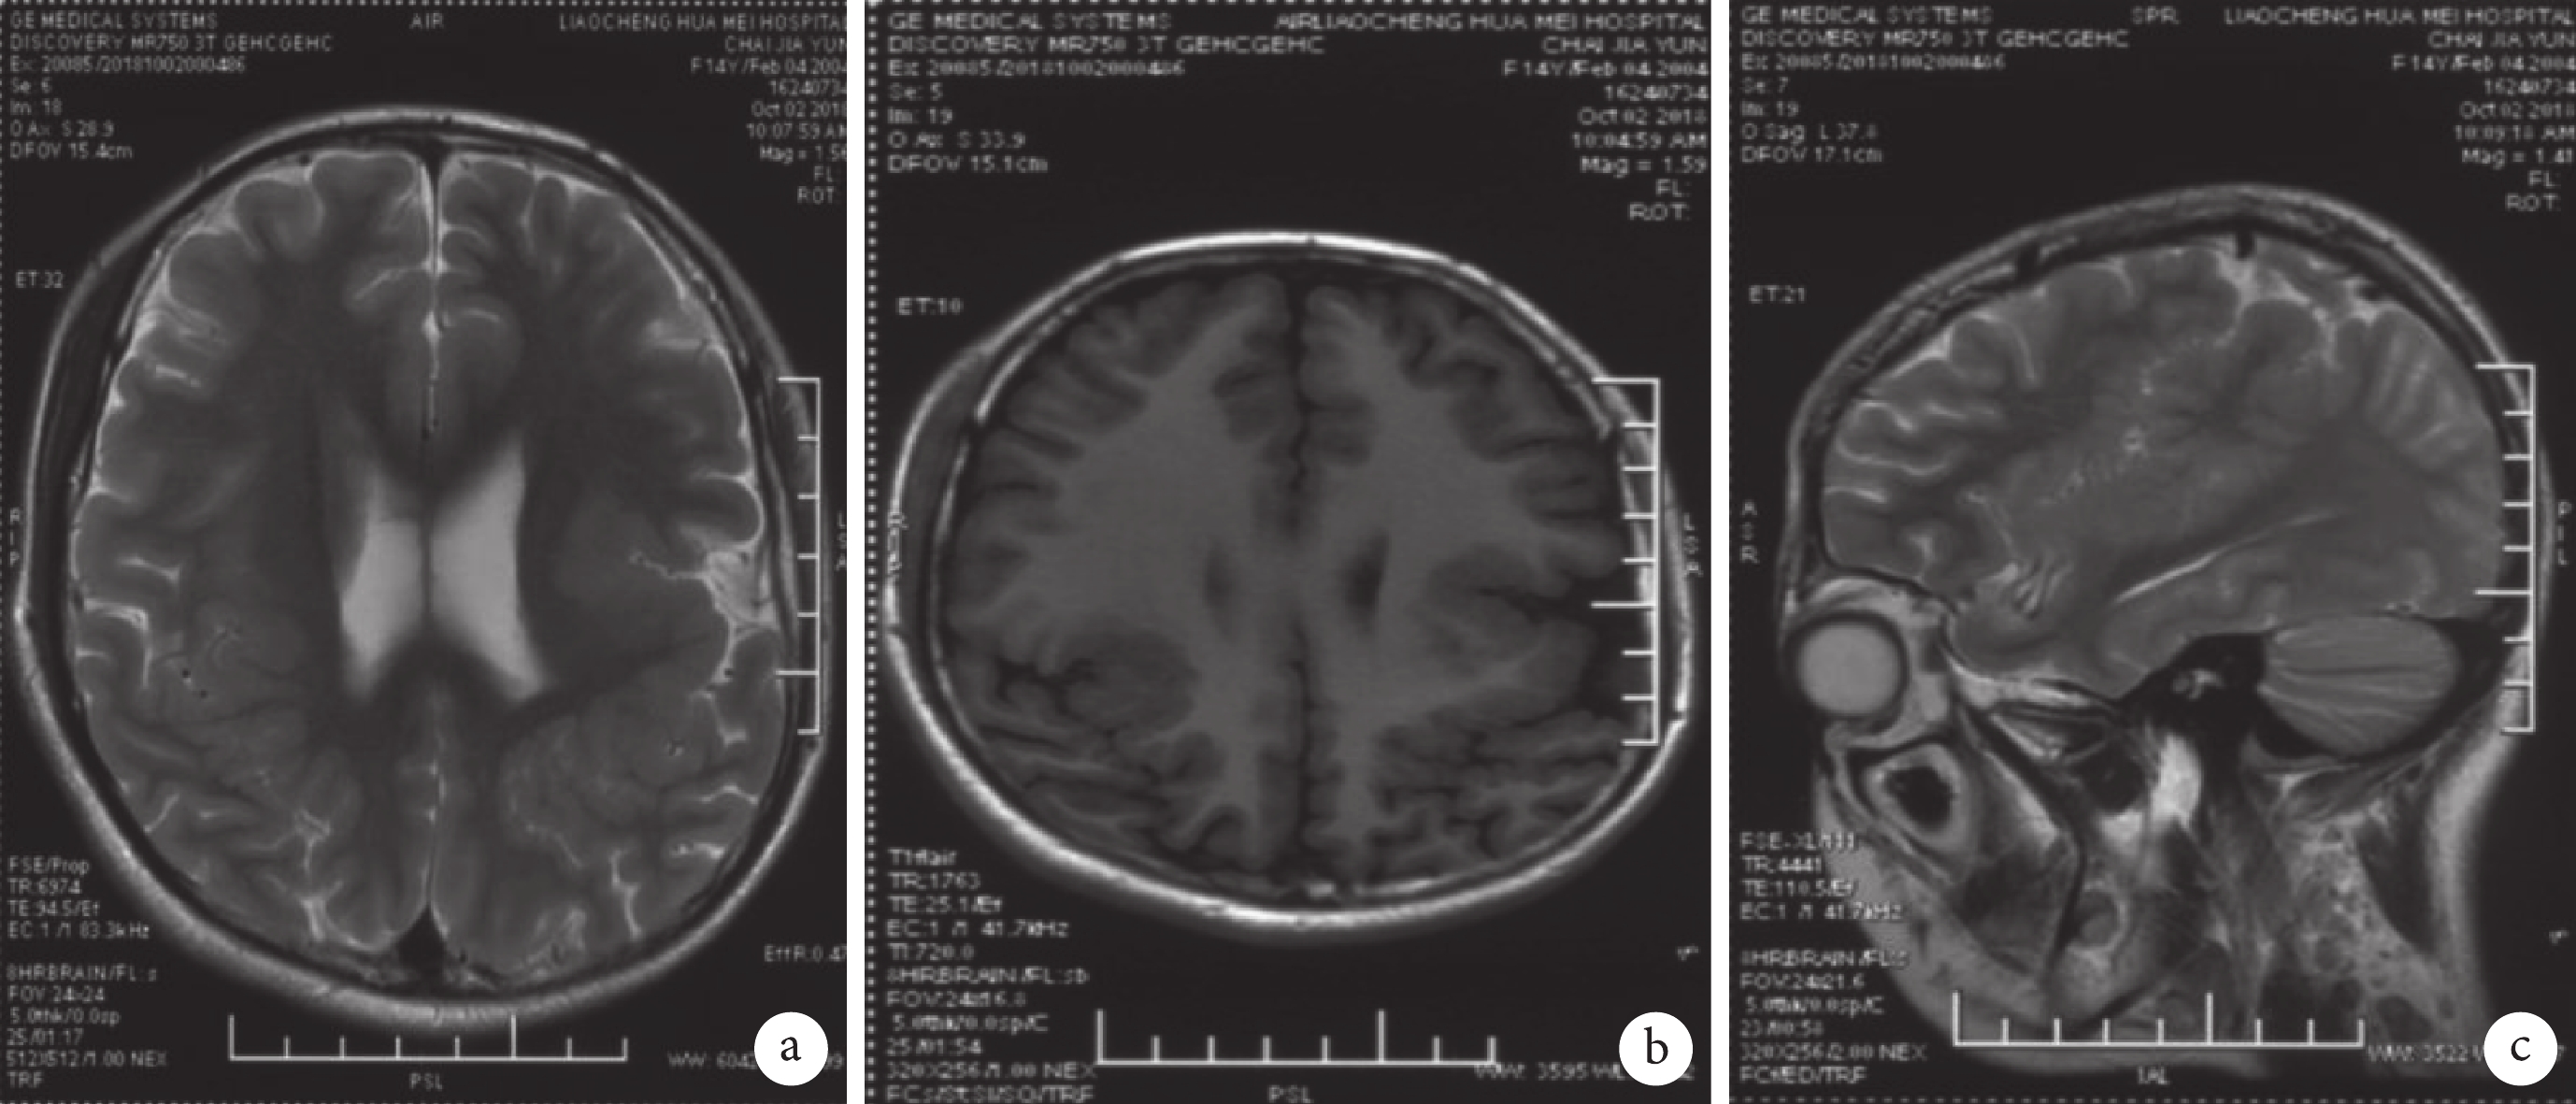

圖4

患者頭部核磁共振成像

a. T2 加權相軸位;b. T1 FLAIR 相軸位;c. T1 FLAIR 相矢狀位(左)。MRI 示雙外側裂形態異常,周圍皮質增厚,左側著矢狀位左島葉灰質異常增厚,正常溝回消失